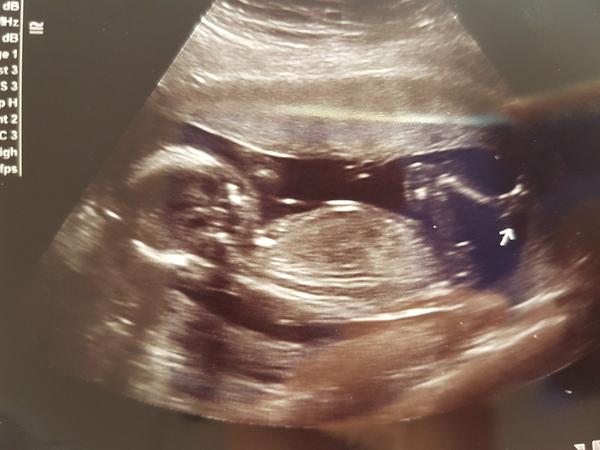

Čau holky, co myslíte u nás? Podle doktora je to "tutovka", tak jsem zvědavá na Vaše názory! 🙂 @innocence nebude spoilerovat! 😀

To vypadá na kluka ne? 🙂

@michalelka je to malinke, ale pokud dobre vidim, tak holka 🙂

@evulka2017 Řekla bych,že kluk 🙂

@evulka2017 kluk?

Kluk...holka má kávové zrnko

@krupka1 prý tam je pinďa.. tak uvidíme 😀

@krupka1 tak dobře, když se tu bude slovíčkařit.. 😂 Podle doktora je to kluk, lepší?